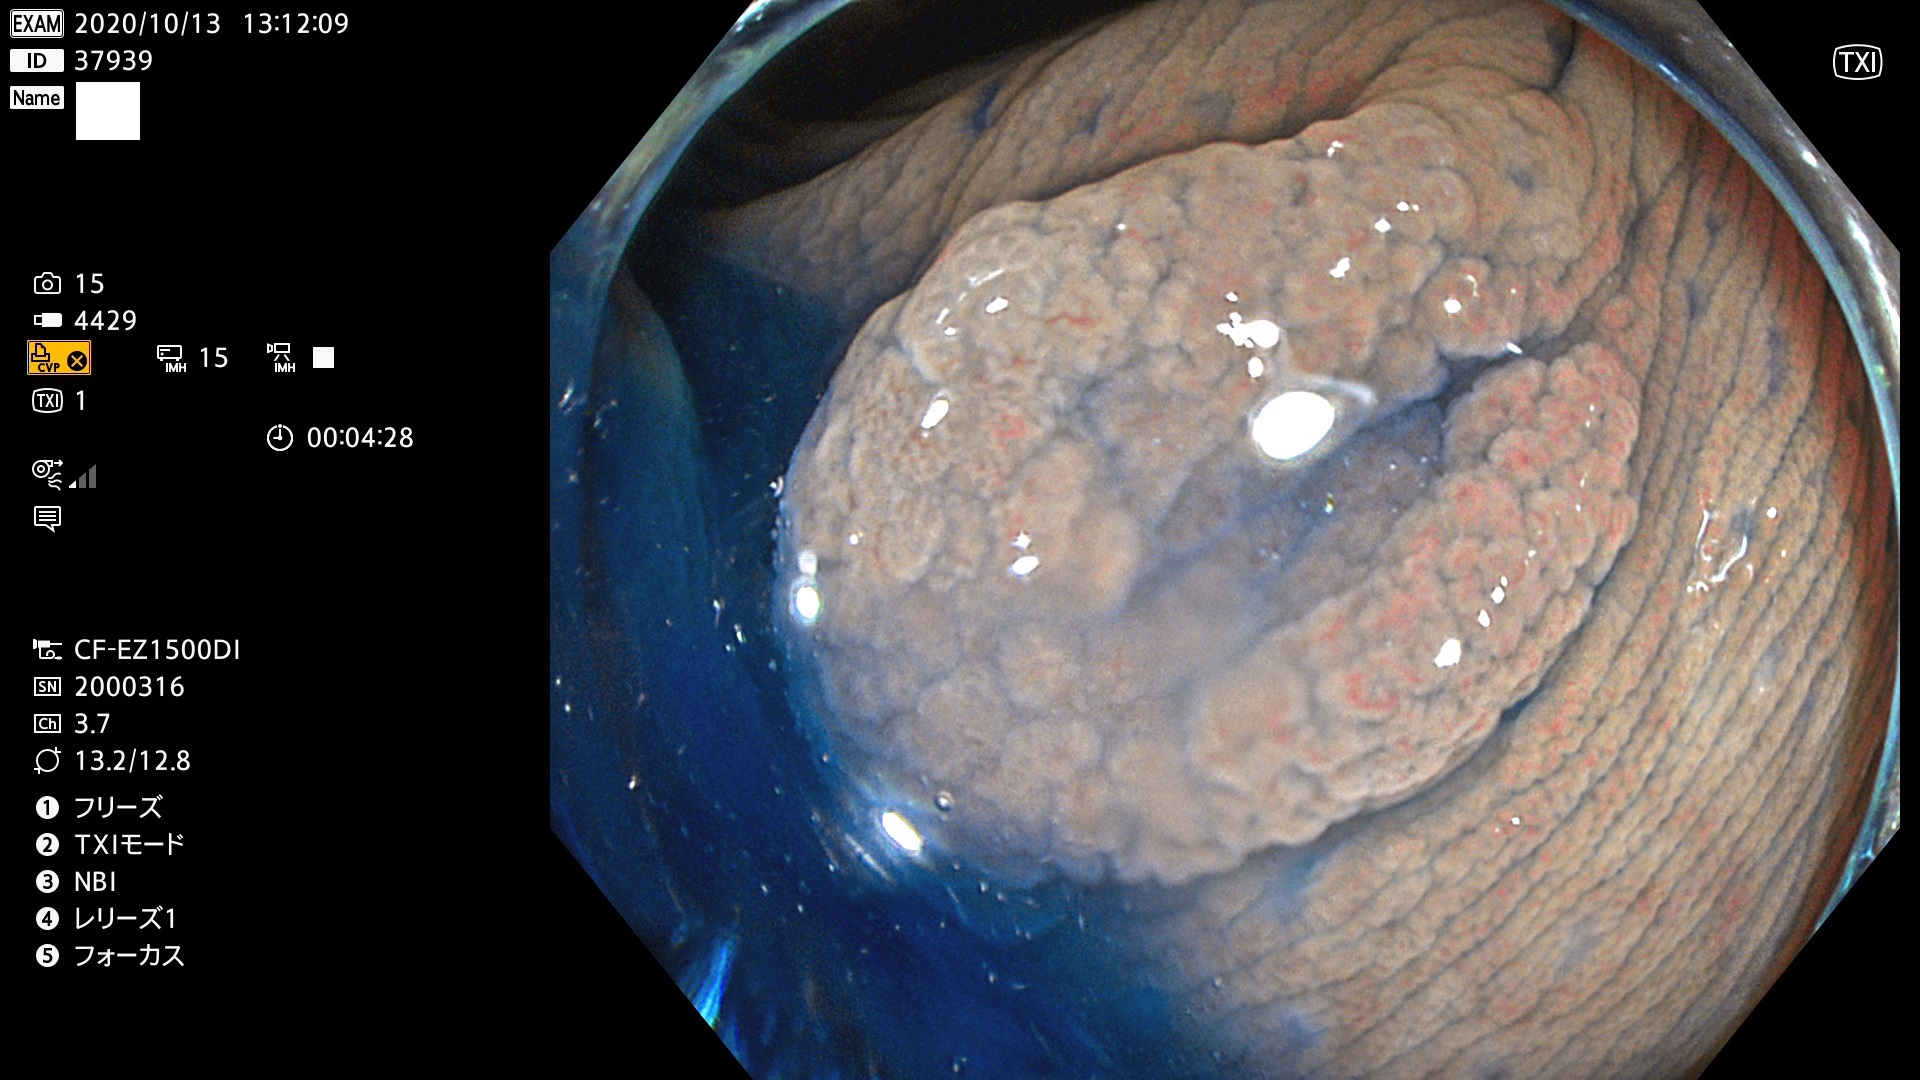

37900 37902 37903 37904 37905 37906 37907 37909 37910 37911 37912 37913 37914 37915 37916 37917 37919 37921 37922 37923 37926 37928 37929 37930 37931 37933 37934 37935 37936 37937 37938(SSAPのみ) 37939 37940 37941 37942 37943 37946 37947 37948 37949 37951 37952 37953(SSAPのみ) 37955 37956 37957(SSAPのみ) 37958(SSAPのみ) 37960 37962 37963 37964 37966 37967 37968 37971 37972 37973 37975 37976 37977 37979 37982 37983 37984 37985 37986 37987 37988 37989 37990 37991 37992 37993 37994 37995 37996 37998 37999

発見困難で危険性の高い平坦型病変(上記100名より抽出)